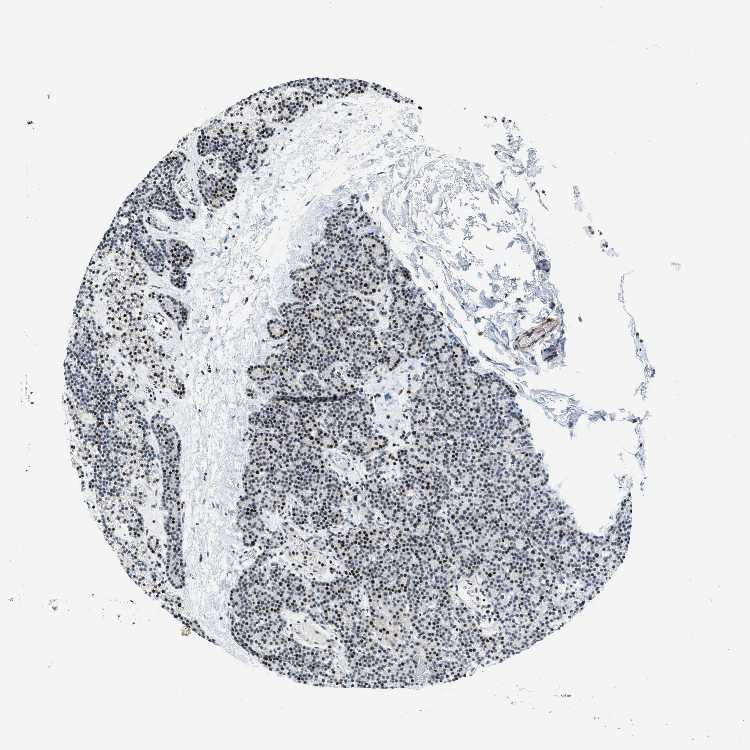

PARATHYROID GLAND - Antibody stainingi

Antibody staining in the annotated cell types in the current human tissue is reported as not detected, low, medium, or high, based on conventional immunohistochemistry profiling in selected tissues. This score is based on the combination of the staining intensity and fraction of stained cells.

Each image is clickable and will lead to virtual microscopy that enables deeper exploration of all samples and also displays staining intensity scores, fraction scores and subcellular localization as well as patient and tissue information for each sample.

Antibody HPA016808

Glandular cells High